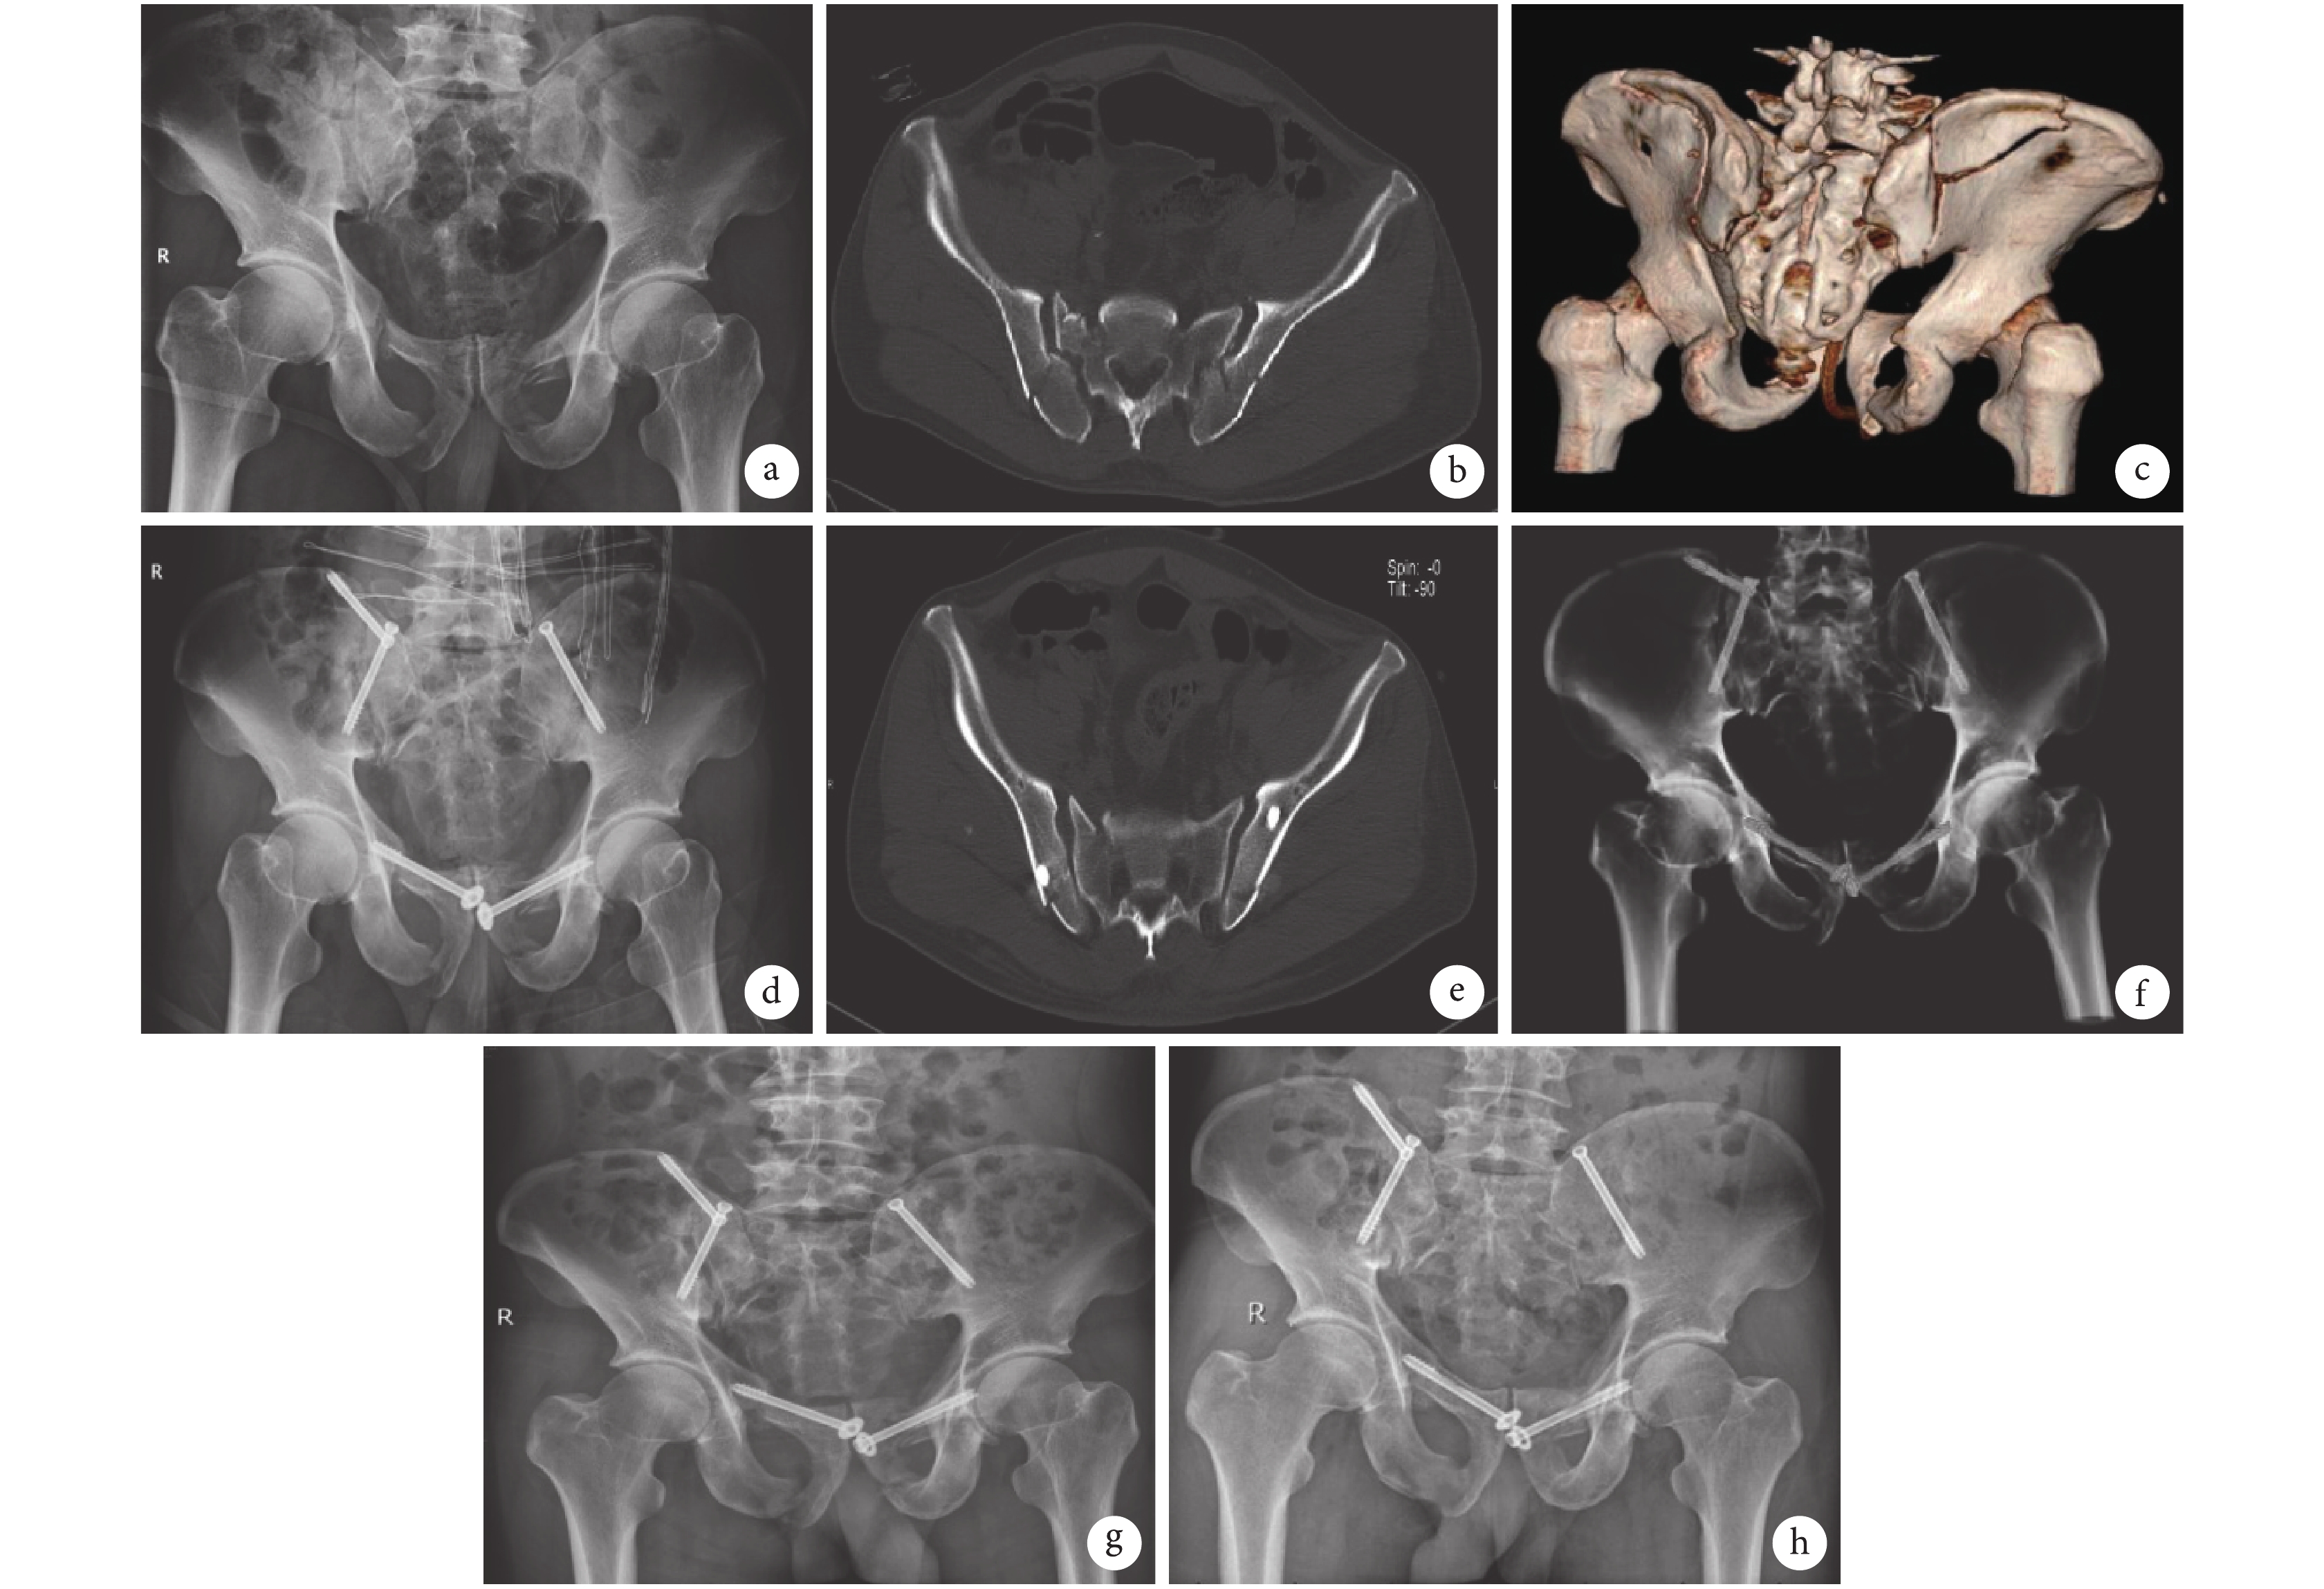

患者 男,52 歲。重物砸傷致胸腹部疼痛 5 h 由外院轉入我院。入院即擴容抗休克,急診行剖左胸探查左側膈疝修補+胸腔閉式引流,剖腹探查+直腸前壁漿肌層破裂修補+股骨髁上骨牽引術。診斷:Tile B 型骨盆骨折,雙側恥骨上下支骨折、骨盆新月型骨折(Day Ⅱ 型)。入院第 7 天行骨盆骨折閉合復位空心螺釘內固定術。先仰臥位固定雙側恥骨上支骨折,再俯臥位固定雙側骨盆新月型骨折;考慮骶髂韌帶復合體無明顯分離損傷,未行骶髂螺釘內固定。術后 X 線片示垂直及旋轉移位基本糾正。術后 3 個月骨折愈合,無螺釘松動、斷裂等并發癥發生。術后 1 年患者工作和生活恢復良好,骶髂部無明顯叩壓痛,但體力勞動及行走過久后骶髂部仍出現輕微酸痛不適,可能與骶髂關節未固定有關。根據 Matta 評價標準評價骨折復位為良,按照 Majeed 功能評分評價功能為良。見圖 1。

a. 術前 X 線片;b. 術前 CT 平掃;c. 術前 CT 三維重建;d. 術后 2 d X 線片;e. 術后 3 d CT 平掃示雙側新月型骨折空心螺釘內固定后骨折線對合可;f. 術后 3 d CT 三維重建示髂骨后柱螺釘及髂骨翼螺釘位置良好,骨盆前后環基本恢復正常;g. 術后 1 個月 X 線片示骨折線模糊,骨折對位對線可;h. 術后 1 年 X 線片示骨折愈合,骨折線消失

Figure1. A typical casea. Preoperative X-ray film; b. Preoperative CT scan; c. Preoperative CT three-dimensional reconstruction; d. X-ray film at 2 days after operation; e. CT scan at 3 days after operation, showing bilateral crescent fractures gained a good position; f. CT three-dimensional reconstruction at 3 days after operation, showing the posterior column screw of the ilium and the iliac wing screw were in good position, the anterior and posterior pelvic ring were generally restored to normal shape; g. X-ray film at 1 month after operation, showing the fracture line was blurred and the fracture alignment was good; h. X-ray film at 1 year after operation, showing the fracture healed and the fracture line disappeared